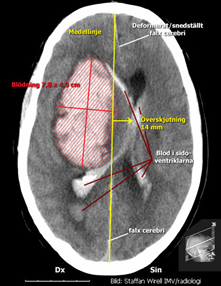

Typ av undersökning? Vad visar bilden?

- DT

- Lateralt om den högra sidoventrikeln finns en 78 x 40 x 70 mm stor blödning med genombrott till ventrikelsystemet. Det finns blod i samtliga ventriklar. Höger hemisfär är avsevärt svullen. Det finns en herniering under falx och medellinjestrukturerna är överskjutna 14 mm åt vänster. Höger sidoventrikel är avsevärt tillklämd/sammanpressad. I cisterna ambiens finns mycket lite liquor, medan övriga basala cisterner och fåror ej är urskiljbara.

På akutmottagningen tar neurologjouren emot och bestämmer sig relativt omgående för att göra en akut datortomografi av hjärnan. Under väntetiden blir Hjalmar allt mer motoriskt orolig och oklar. Narkosläkare tillkallas och man tvingas söva och intubera patienten för att kunna genomföra röntgenundersökningen. Neurologjouren meddelas röntgensvaret och tillkallar omgående neurokirurgjouren. Då hon ser patienten på akuten är han sövd men nu är höger pupill större än vänster och de drar endast ihop sig trögt och ytterst lite då man lyser i dem. Patientens puls har börjat sjunka och är nu nere på 40/min. Hon beslutar om utrymning av hematomet och Hjalmar förs omedelbart till operationssalen. Under transporten dit får han intravenöst Mannitol och hyperventileras.

- Scenariot beskriver en typisk s k hypertoniblödning i hjärnan och det urakuta förlopp som kan följa med blödningens tilltagande intrakraniella volymexpansion med tillhörande motorisk oro hos patienten, senare medvetslöshet och vid hotande inklämning över tentorieslitsen påverkan på den ipsilaterala nervus oculomotorius samt s.k. Cushingreaktion (stegrande blodtryck, oregelbunden andning och bradykardi

Om förhöjt intrakraniellt tryck (ICP) inte behandlas, eller om förloppet är mycket snabbt, kan inklämning, s.k. herniering, ske. Det innebär att hjärnparenkymet kläms åt av det höga trycket mot de styva strukturer i skallen som finns, företrädesvis de durala skiljeväggarna. Man brukar tala om två huvudtyper av inklämning, vilka?

- Subfalcin – när ena hemisfärens mediala del, oftast frontalloben och gyrus cinguli kläms under falx cerebri.

- Transtentoriell hernierning – om det rör sig om en temporalt belägen expansivitet. Innebär att mediala temporalloben med uncus hernierar ned medialt om tentorium cerebelli och kardinaltecknet är ipsilateral pupilldilatation (mydriasis), vilket orsakas av att de ytligt belägna parasympatiska fibrerna av n. oculomotorius till m. sphincter pupillae komprimeras